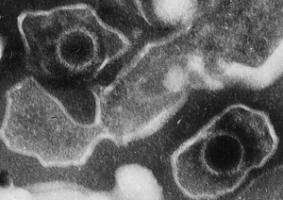

Actualité publiée le 23/09/2016STRESS: Il réveille l'Herpèsvirus qui dort